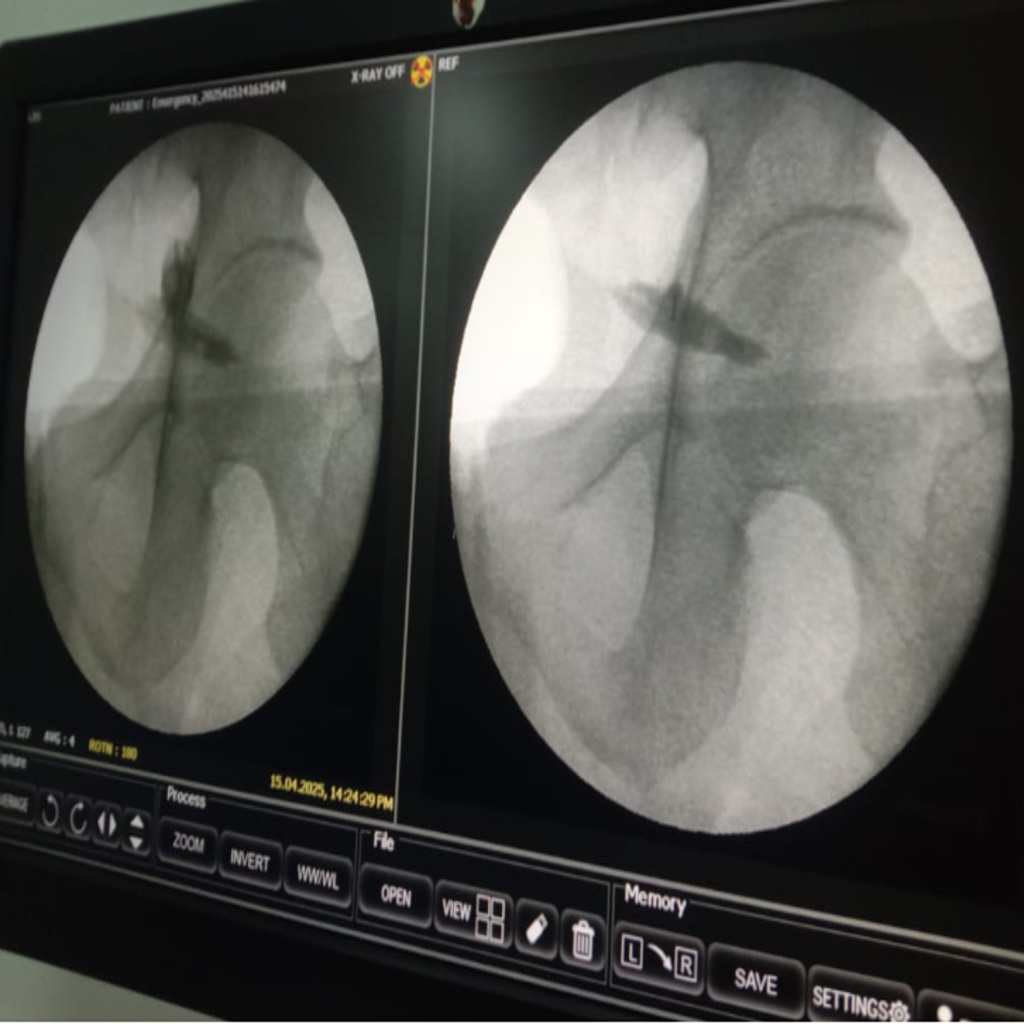

Fluoroscopy guided Injection for Piriformis Syndrome being carried out at Alleviate Pain Clinic, Bengaluru. Image Courtesy- Alleviate Pain Clinic

Image-guided precision treatments include:

- Lumbar facet joint injections for facet arthritis

- Medial branch blocks & radiofrequency ablation for chronic facet pain

- Sacroiliac joint injections for SI dysfunction

- Piriformis muscle injections (ultrasound-guided)

- Epidural or nerve root blocks for disc-related sciatica